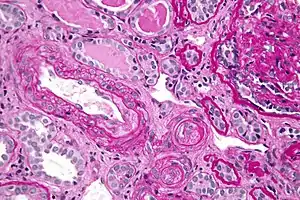

Micrograph showing thrombotic microangiopathy, the histomorphologic finding seen in scleroderma renal crisis, kidney biopsy, PAS stain

Kidney involvement, in scleroderma, is considered a poor prognostic factor and frequently a cause of death.[13]

The most important clinical complication of scleroderma involving the kidney is scleroderma renal crisis (SRC), the symptoms of which are malignant hypertension (high blood pressure with evidence of acute organ damage), hyperreninemia (high renin levels), azotemia (kidney failure with accumulation of waste products in the blood), and microangiopathic hemolytic anemia (destruction of red blood cells).[14] Apart from the high blood pressure, hematuria (blood in the urine) and proteinuria (protein loss in the urine) may be indicative of SRC.[15]

In the past, SRC was almost uniformly fatal.[16] While outcomes have improved significantly with the use of ACE inhibitors,[17][18] the prognosis is often guarded, as a significant number of patients are refractory to treatment and develop kidney failure. About 7–9% of all diffuse cutaneous scleroderma patients develop renal crisis at some point in the course of their disease.[19][20] Patients who have rapid skin involvement have the highest risk of renal complications.[21] It is most common in diffuse cutaneous scleroderma, and is often associated with antibodies against RNA polymerase (in 59% of cases). Many proceed to dialysis, although this can be stopped within three years in about a third of cases. Higher age and (paradoxically) a lower blood pressure at presentation make dialysis more likely to be needed.[22]